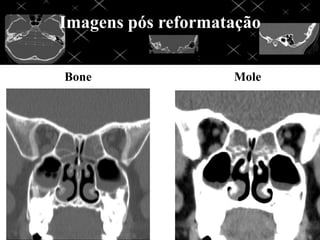

Imagens reformatadas

Bone Mole

Imagens pós reformatação